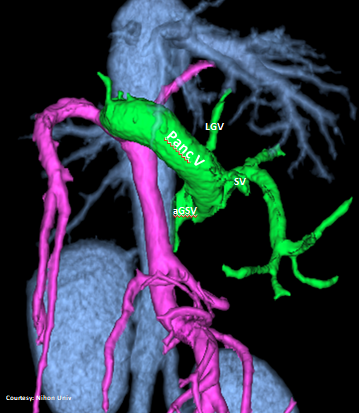

slide50

POST-HEPATIC ENTRANCE

(Left Hepatic Vein Entrance)

“LGHV +PancV -GSV”

Left Gastric – Left Hepatic Vein Shunt with Pancreatic Vein contribution and absent Gastrosplenic Vein

WEISSE 2022